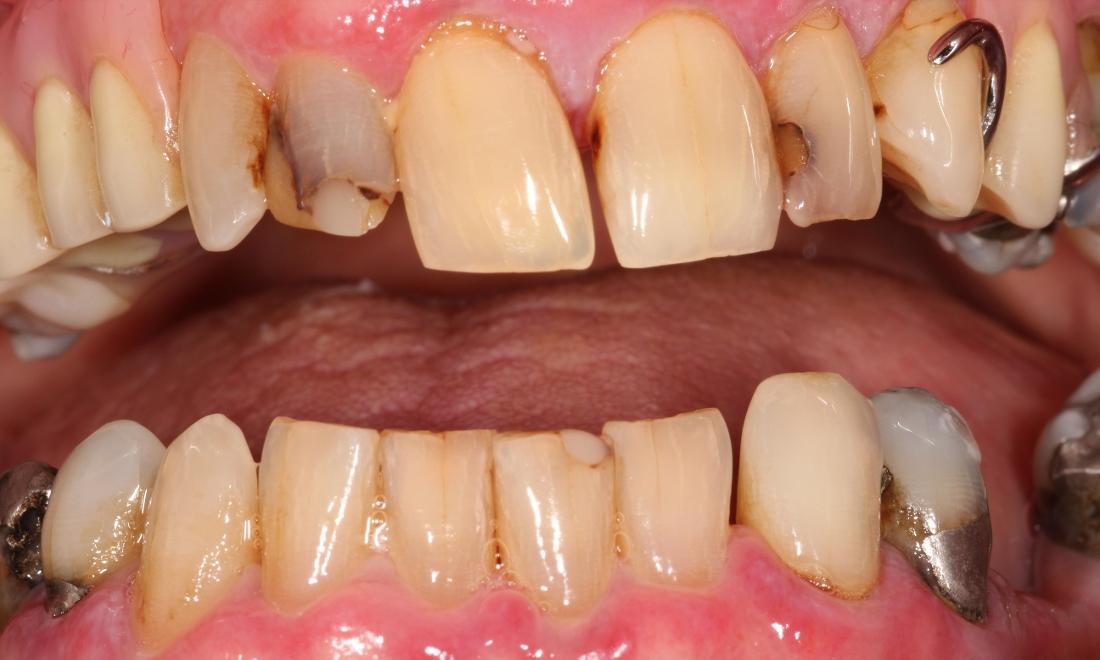

Crown Restorations

Upper (maxillary) crown work completed around upper partial denture. We removed the decay in these teeth, prepped them, and placed six anterior crowns for a beautiful result!